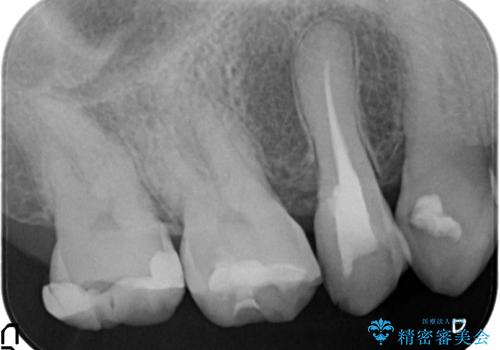

診査の結果痛みの原因は右上7番目だったため、古い樹脂と虫歯を除去後、オールセラミッククラウンによる補綴を行いました。

また右上5、6番目の歯も治療を希望されたため、オールセラミッククラウンによる補綴を行いました。

根管治療の注意事項(リスク・副作用など)

- 根管治療により痛みや腫れがひかない事や、術後に痛みや腫れが生じる事、治療によるファイル破折やパーフォレーションなどの偶発症、術後の歯根破折を生じる可能性もあります